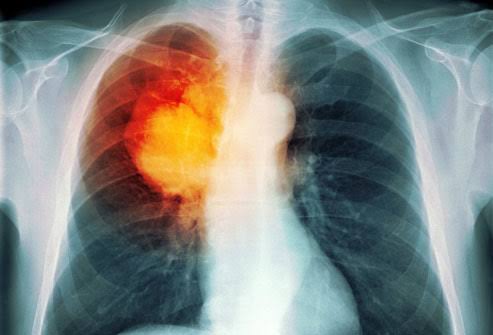

أورام الرئة من أشد وأخطر الأورام السرطانية التي تهدد صحة الفرد وقد تودي بحياة الفرد، ويعد سرطان الرئة أكثر أنواع السرطان شيوعًا في العالم لعدة أعوام، وبحلول عام 2008، كان هناك ما يقدر بمليون و610 ألف حالة جديدة، وهو ما يمثل 12.7٪ من جميع حالات السرطان الجديدة.

ويعتبر أيضًا السبب الأكثر شيوعًا للوفاة من السرطان، بواقع مليون و380 ألف حالة وفاة، أي ما يعادل 18.2 % من مجموع الحالات.

سرطان الرئة هو نمو غير متحكم به لخلايا غير طبيعية في إحدى أو كلتا الرئتين، وهذه الخلايا الغير طبيعية لا تقوم بمهام خلايا الرئة الطبيعية ولا تتطور إلى أنسجة رئة سليمة، فتتشكل الأورام و تعيق عمل الرئة.